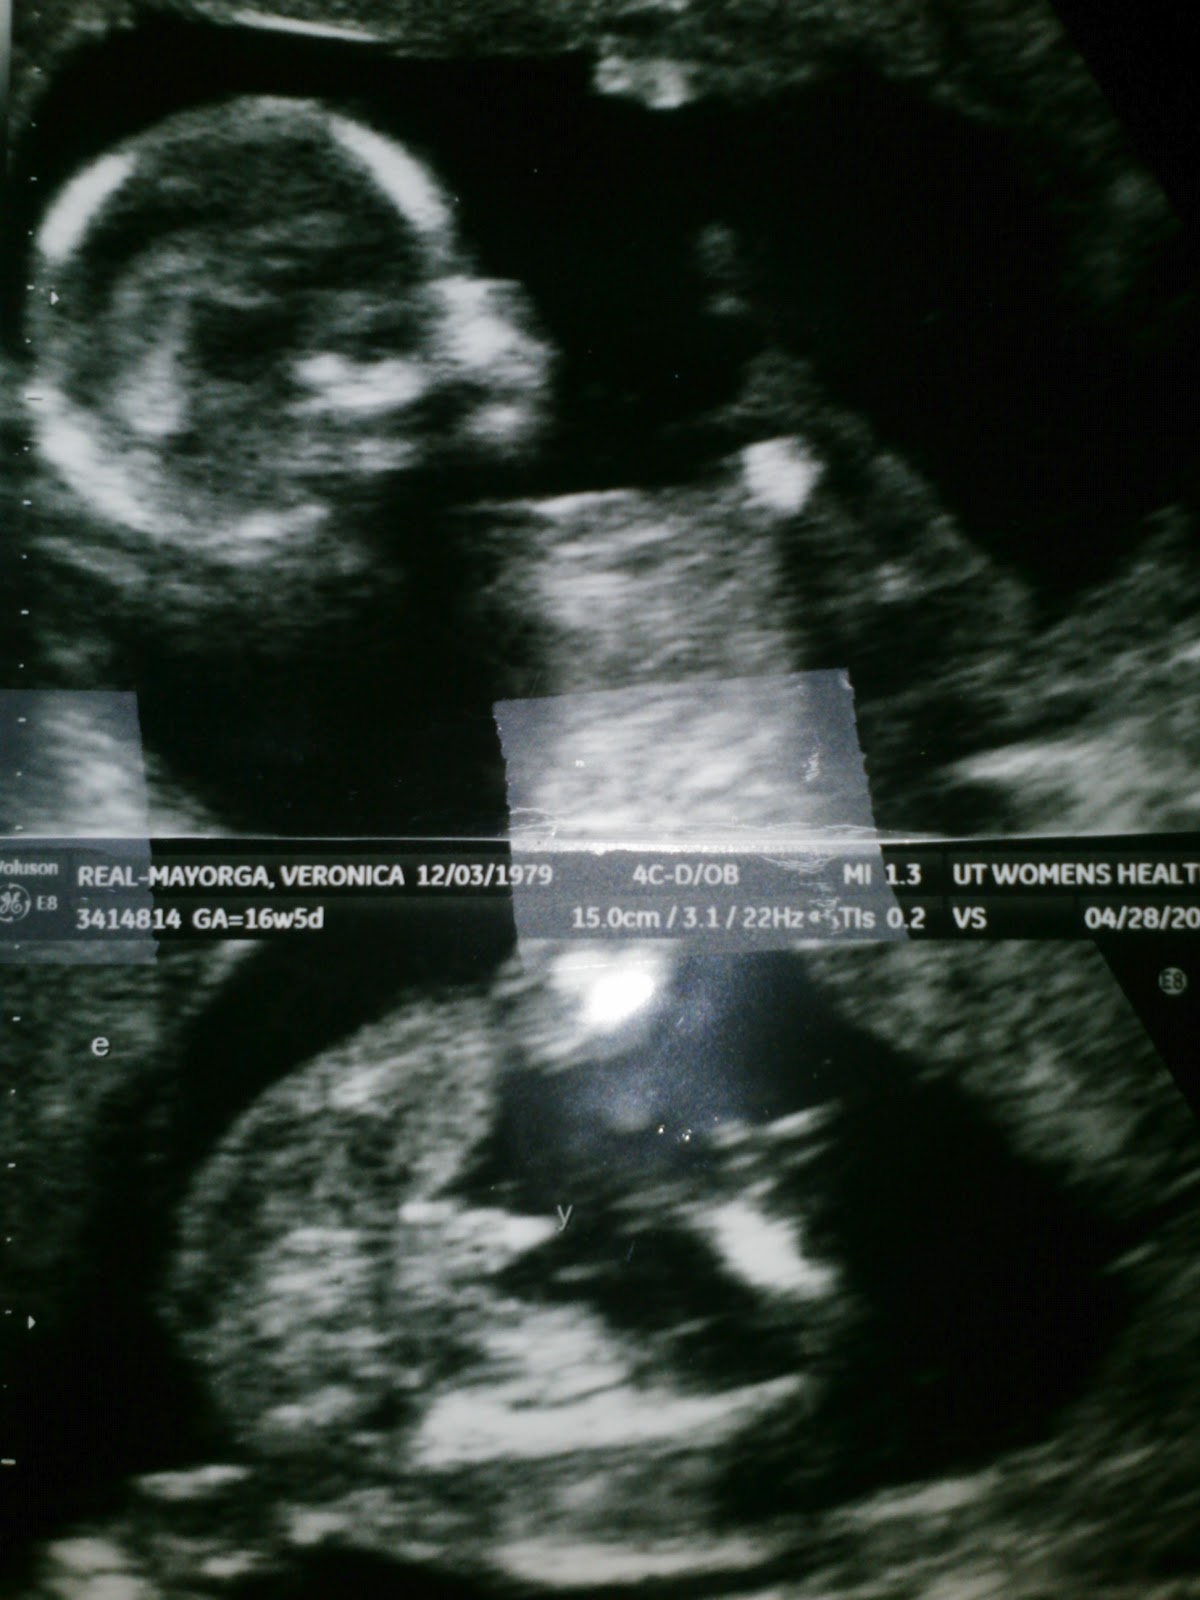

I had my 4th. ultrasound done and my husband Enrique and my son Fernando came with me. The ultrasound that the tech did today was more detailed. I was on my back for more than 3 hours because they wanted to measure them and check they're growing properly. Also, I was told how many boys and how many girls I'm having !!!!

Quint A is a Boy...

Quint B is...... a Girl

Quint C is a Boy

Quint D is a Girl

and finally....... Quint E is a Boy.